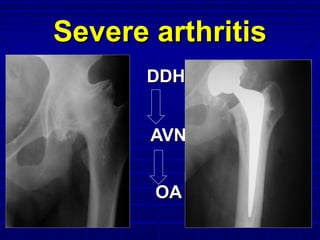

Consider for:Consider for:

 Severe arthritisSevere arthritis

 Failed “Failed “

conservative”conservative”

Rx.Rx.

 BilateralBilateral

diseasedisease

Severe arthritisSevere arthritis

DDHDDH

AVNAVN

OAOA